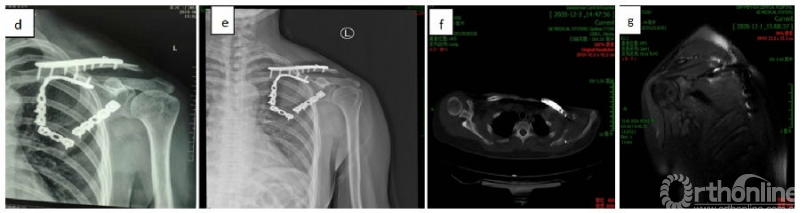

术后复查影像学资料

注:图d为2019.06.18复查的X线片,提示左锁骨远端溶解;图e、f、g为2020.11.30复查的X线、CT、MRI,提示左锁骨远端缺失,核磁压脂像上未见明显的混杂信号。